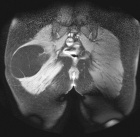

50 year old female presents with c/o enlarging mass in L buttock region. Hx of having had a mass excised from this same area five years earlier.

Zoom image: Radiological image Radiological image.